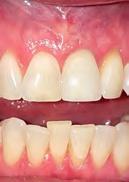

6. Images 6a & 6b: 2-week post-operative follow-up.

7. Images 7a & 7b: Final restoration at 16 months post-operative.